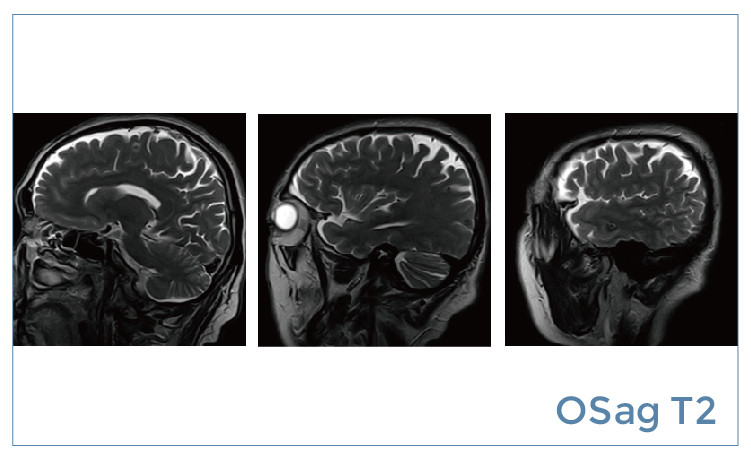

【朗润影像档案】磁共振影像病例分享(编号20190524)